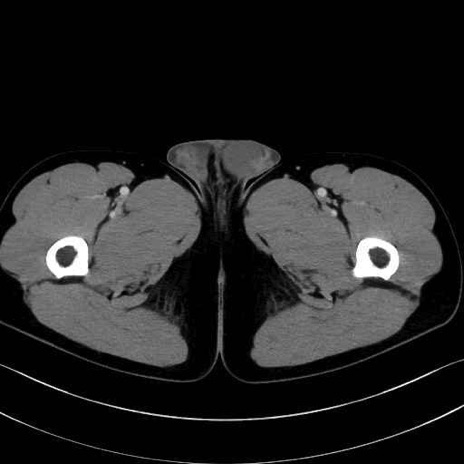

肛門挙筋(levator ani muscle)のCT画像の解剖

肛門挙筋 (Levator ani)

内閉鎖筋 (Obturator internus)